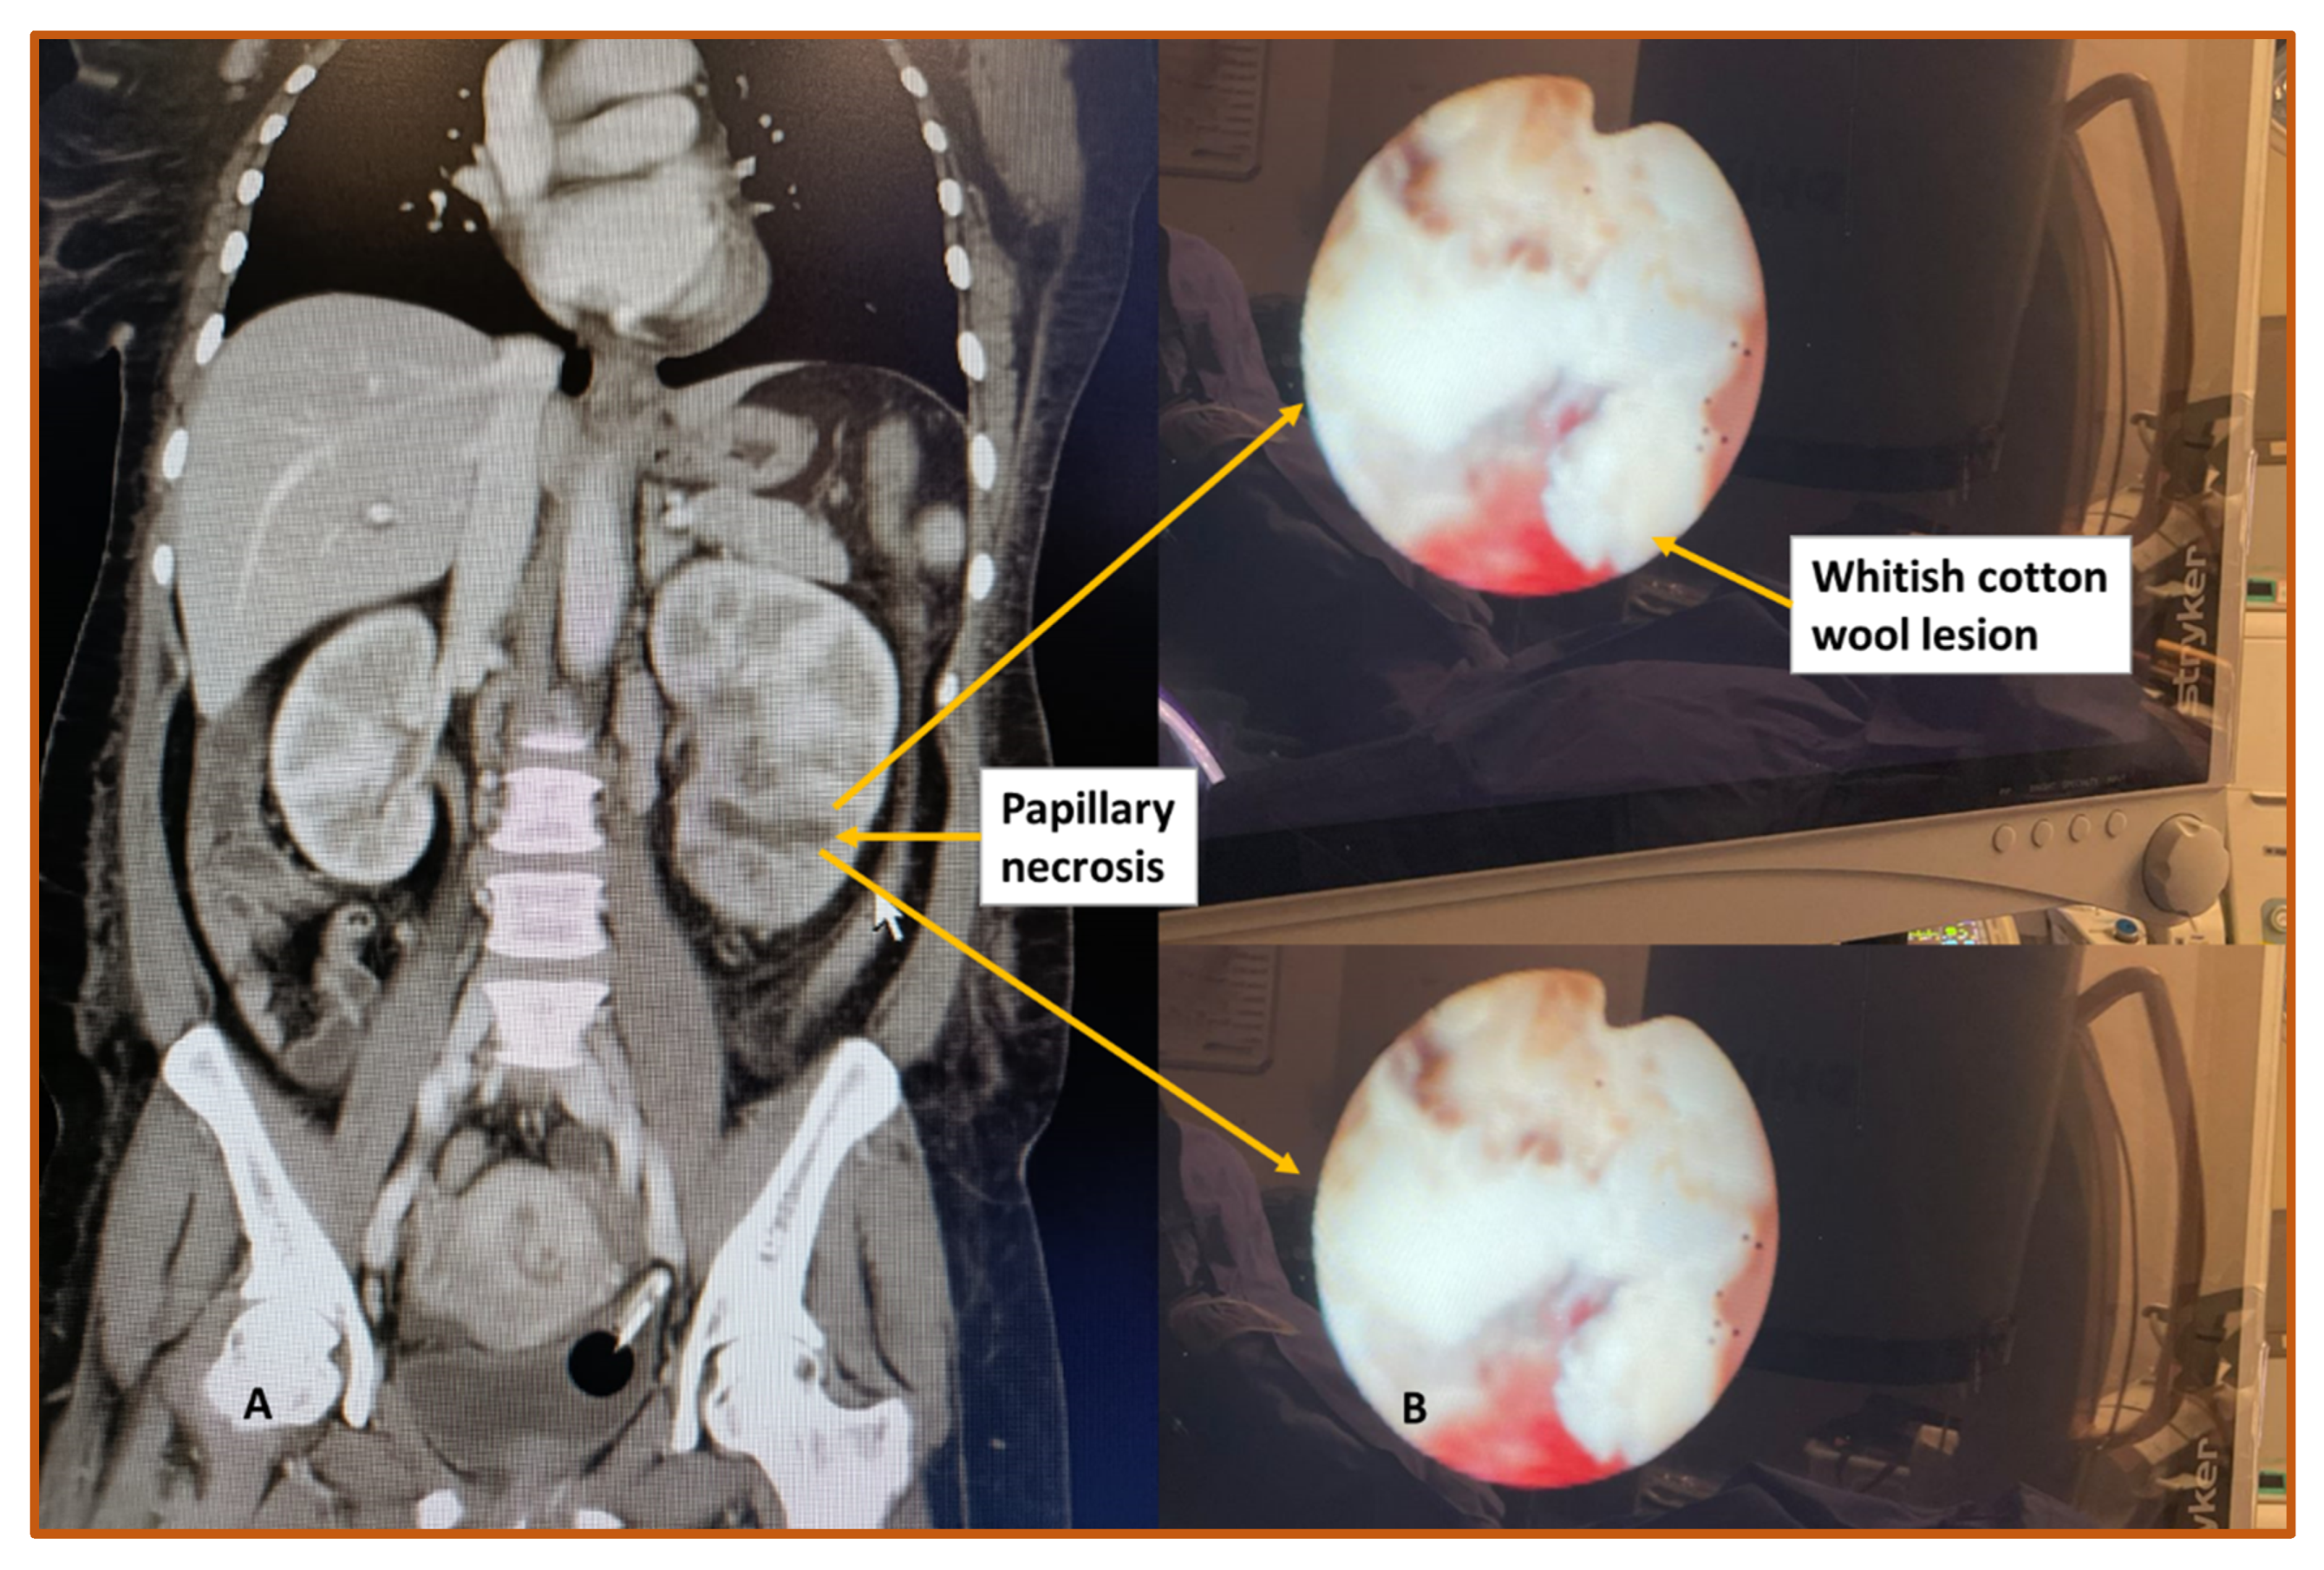

- Jung, D.C.; Kim, S.H.; Jung, S.I.; Hwang, S.I.; Kim, S.H. Renal papillary necrosis: Review and comparison of findings at multi–detector row CT and intravenous urography. Radiographics 2006, 26, 1827–1836. [Google Scholar] [CrossRef]

- Lang, E.; Macchia, R.; Thomas, R.; Davis, R.; Ruiz-Deya, G.; Watson, R.; Richter, F.; Gayle, B. Detection of medullary and papillary necrosis at an early stage by multiphasic helical computerized tomography. J. Urol. 2003, 170, 94–98. [Google Scholar] [CrossRef]